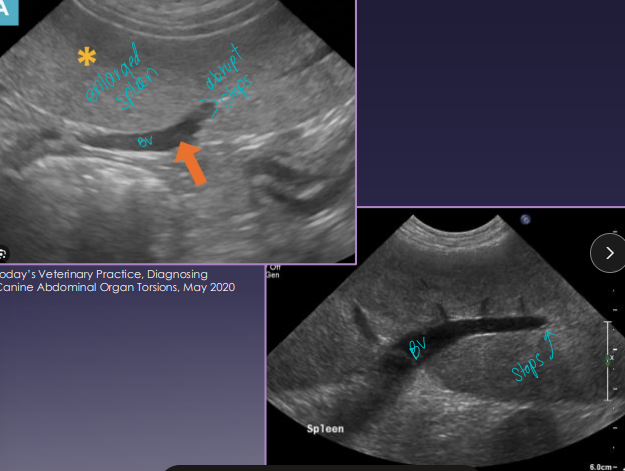

Splenic Torsion “acute abdomen”

US: variable echotexture, dilated vessels, thrombi

Splenic Neoplasia

Dt: Abd rads (mass effect, effusion, metastasis), US (mixed echotexture, cavitated lesions, enlarged spleen), biopsy